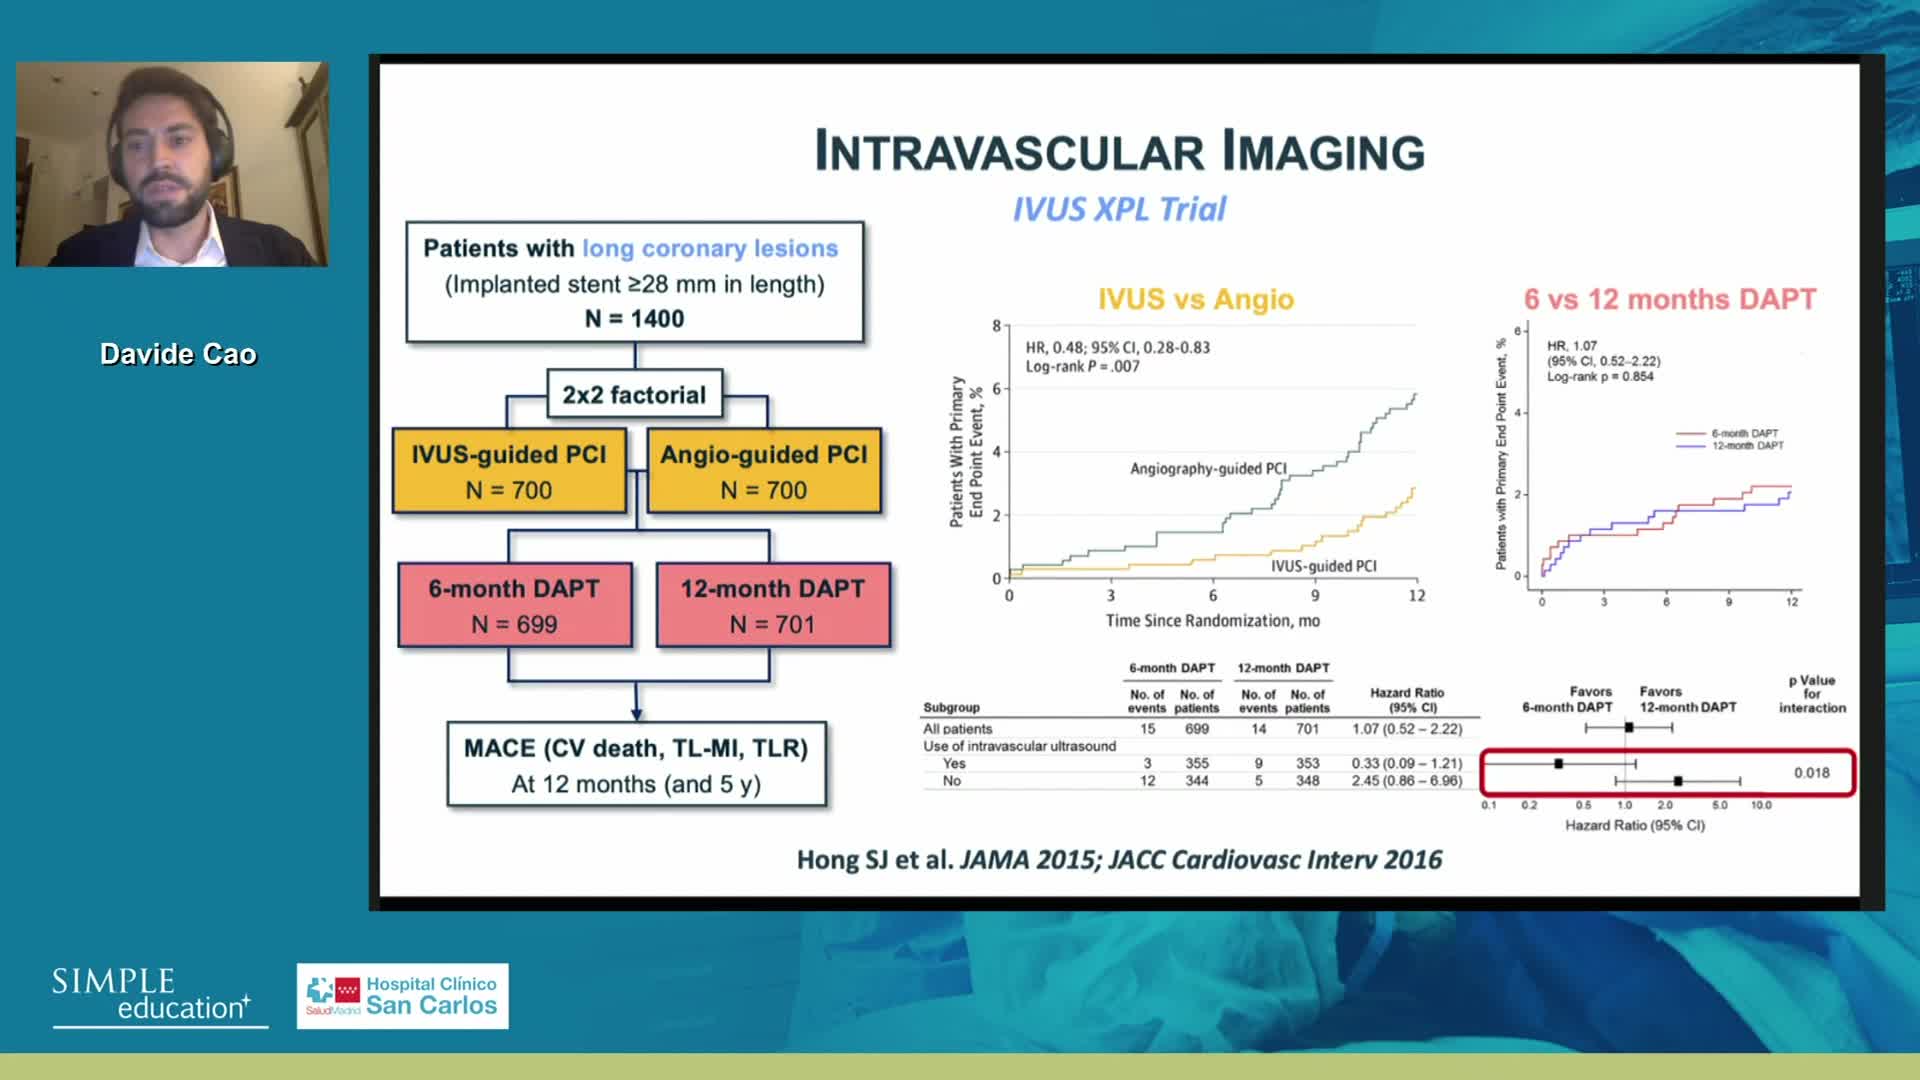

Evidence base for IVUS: to support use in routine practice - Prof Erick Schampaert

How to perform good co-registration measurements using iFR and IVUS - Prof Carlo Di Mario

Using SyncVision Co-registration to distinguish between focal and diffuse coronary disease. - Prof Giuseppe Tarantini

Coronary Bifurcations: An Update on Diagnosis, PCI planning and Imaging and PhysiologyGuidance - Dr Dejan Milasinovic